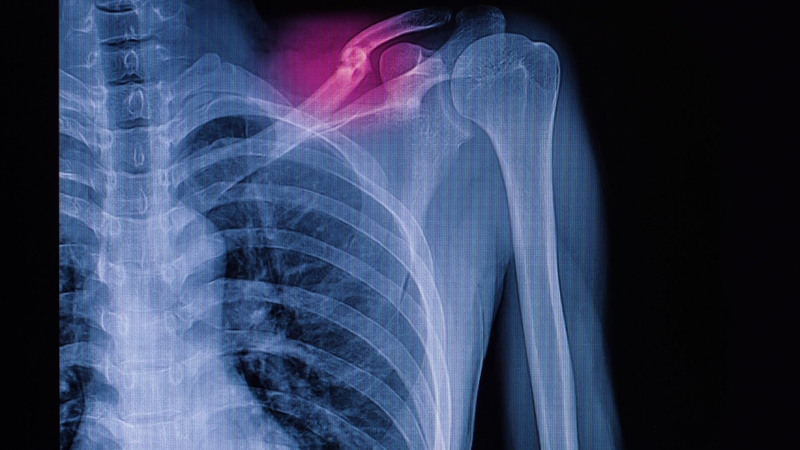

Hình ảnh X-quang xương đòn bị gãy sẽ như thế nào?

Mô tả hình ảnh X-quang xương đòn bị gãy

Kỹ thuật chụp X-quang xương đòn thẳng thường được áp dụng khi bệnh nhân nghi ngờ bị chấn thương xương đòn, một dạng chấn thương phổ biến chiếm khoảng 2,6-5% trong các trường hợp gãy xương.

Khi gặp các triệu chứng lâm sàng nghi ngờ gãy xương đòn, bác sĩ chuyên khoa sẽ chỉ định chụp X-quang xương đòn thẳng để xác định chính xác tình trạng chấn thương.

Kết quả trên phim X-quang:

• Tiêu chuẩn phim X-quang xương đòn: Hình ảnh phải bao quát toàn bộ xương đòn và cả hai khớp liên quan. Xương đòn bên được chỉ định chụp phải nằm ở vị trí trung tâm của phim. Phim chụp cần đảm bảo độ nét, độ tương phản rõ ràng, bề mặt sạch và không bị trầy xước.

• Gãy xương đòn được xác định qua hình ảnh mất liên tục của xương trên phim X-quang, thể hiện bằng đường nứt trên xương. Có hai loại gãy là gãy không di lệch, trong đó hai đầu xương gãy vẫn chạm nhau, và gãy di lệch, khi hai đầu xương tách xa nhau.

• Vị trí gãy xương đòn được phân chia thành ba phần: 1/3 ngoài, 1/3 giữa và 1/3 trong.

• Hình ảnh từ phim chụp X-quang cho phép xác định các thông tin quan trọng về tình trạng gãy xương, bao gồm khả năng có di lệch hay không, mức độ di lệch nhiều hay ít, và sự hiện diện của mảnh xương rời.

• Ngoài ra, phim X-quang còn giúp đánh giá các biến chứng có thể xảy ra, như tổn thương thần kinh nghiêm trọng và tình trạng rách hoặc đứt mạch máu, đặc biệt là khi có sự kết hợp với các loại gãy khác.

Dựa trên kết quả hình ảnh gãy xương đòn và kết quả thăm khám, bác sĩ sẽ đưa ra chỉ định điều trị phù hợp. Trong trường hợp xương gãy bị di lệch, phẫu thuật sẽ là cần thiết để nắn chỉnh lại xương cho ngay ngắn và cố định xương gãy ở vị trí tối ưu, đảm bảo quá trình hồi phục diễn ra thuận lợi.